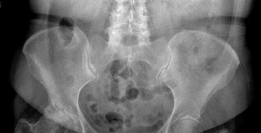

A 55-year-old man is brought to the emergency department after a road traffic accident in which he was the dr…

A 20-year-old man is brought to the emergency department following a high-speed road traffic accident in whic…